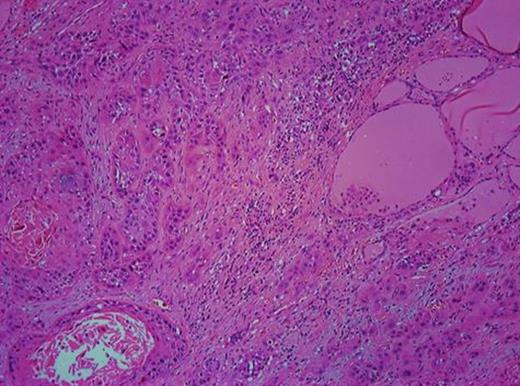

H/E ×100 section from the left lobe of the thyroid gland showing infiltrative SCC.